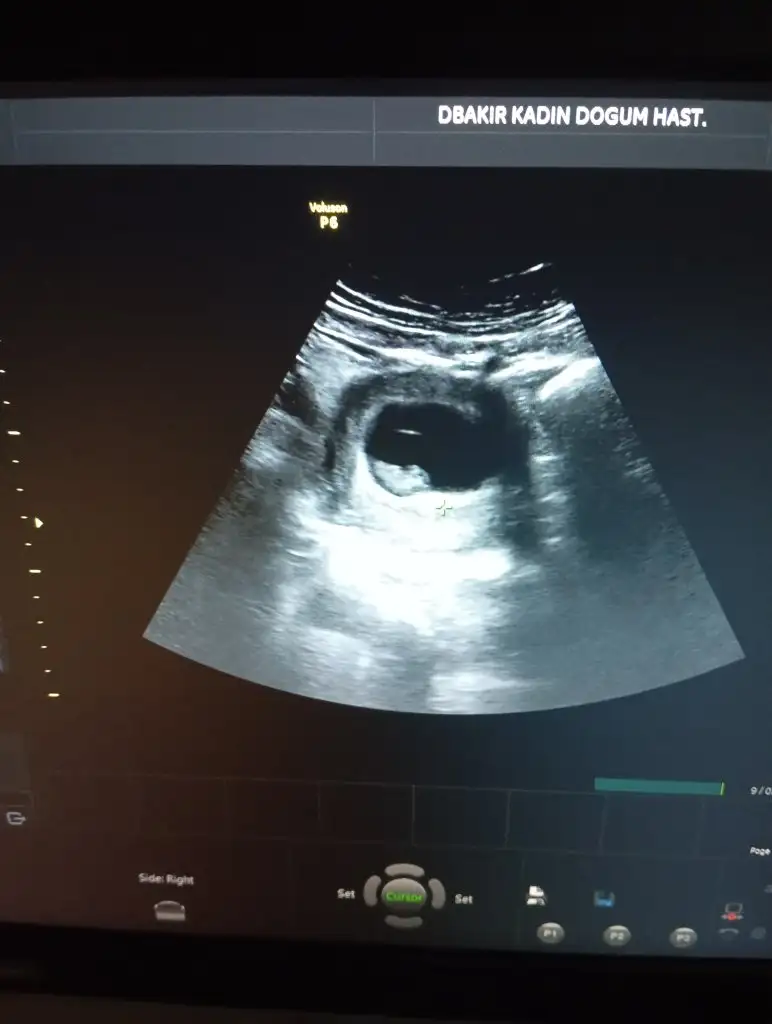

İlk ultrason resimlerinizi paylaşın ramzi teorisine göre cinsiyeti tahmin edeyim bakalım tutacak mı?

Ramzi teorisine göre cinsiyet tahmini yapacagim ilk ultrasyon resminizi atin bakiyim. Eger cinsiyetiniz belliyse hic söylemeeyin bakalm dogru tahmin edebilecekmiyim daha dogrusu ramzi teorisi hakli cikacak mi?